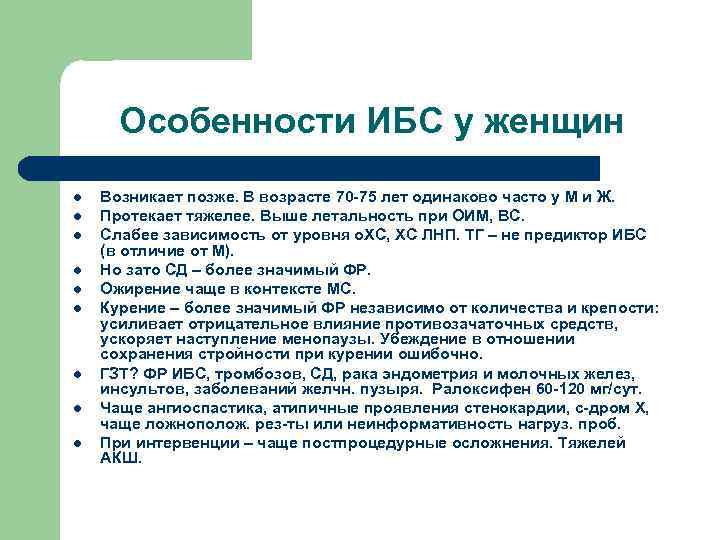

Особенности ИБС у женщин l l l l l Возникает позже. В возрасте 70 -75 лет одинаково часто у М и Ж. Протекает тяжелее. Выше летальность при ОИМ, ВС. Слабее зависимость от уровня о. ХС, ХС ЛНП. ТГ – не предиктор ИБС (в отличие от М). Но зато СД – более значимый ФР. Ожирение чаще в контексте МС. Курение – более значимый ФР независимо от количества и крепости: усиливает отрицательное влияние противозачаточных средств, ускоряет наступление менопаузы. Убеждение в отношении сохранения стройности при курении ошибочно. ГЗТ? ФР ИБС, тромбозов, СД, рака эндометрия и молочных желез, инсультов, заболеваний желчн. пузыря. Ралоксифен 60 -120 мг/сут. Чаще ангиоспастика, атипичные проявления стенокардии, с-дром Х, чаще ложнополож. рез-ты или неинформативность нагруз. проб. При интервенции – чаще постпроцедурные осложнения. Тяжелей АКШ.